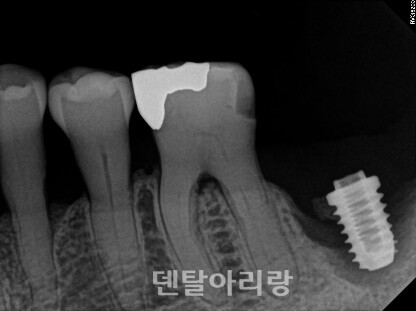

△그림 13. 치조정 접근법에 의한 임플란트 식립 후, 상악동내 출혈

이런 경우, 구강 내로는 출혈이 없이 상악동과 상악동을 통해 비강으로 연결되는 매우 심각한 비출혈이 일어나며, 지혈이 어렵기 때문에 대부분 응급 상황으로 이어지게 된다. 따라서, 치조정 접근법을 통해 임플란트 식립 후, 구강내 출혈이 없더라도 환자가 수술 직후, 또는 귀가 후에 다량의 비출혈 증상을 호소하면 응급실을 통한 구강악안면외과 전문의에게 즉시 의뢰하여야 한다.